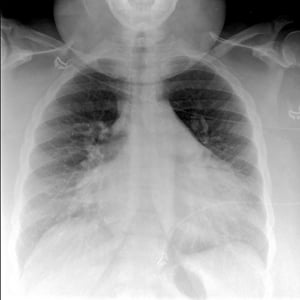

胸部X线检查

胸部X线片,必须立即做,具有较高的诊断价值,可见明显肺间质水肿。床旁测定血清BNP/NT-proBNP水平对鉴别诊断有帮助(肺水肿BNP升高,COPD加重的患者BNP正常)。